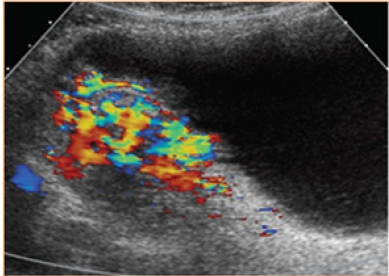

Accreted Placenta Spectrum (AP) is the general term applied to abnormal adherence of the placental trophoblast to the uterine myometrium, also known as morbidly attached placenta. Placental accreta includes placenta accreta (fixation of the placenta to the myometrium without intervening (deci-dua), placenta increta (invasion of the trophoblast to the myometrium), and placenta percreta (PP) (invasion through the myometrium, serous, and surrounding structures) [1]; Figure 1. The first PA case reports were published in the literature in 1920, the first series in 1937 by obstetrician Frederick C. Irving and pathologist Arthur TH of the Boston Lying-In Hospital [2]. Risk factors are any procedure or manipulation that damages the endometrium, including uterine curettage, myomectomy, endometrial ablation, uterine artery embolization, or manual removal of the placenta [1]. The fetus and maternal complications are mainly the result of massive bleeding. In turn, this leads to disseminated intravascular coagulation, multiorgan failure, the need for additional surgery that includes hysterectomy, thromboembolism, and even death. The median estimated blood loss in cohorts of acrets ranges from 2,000 to 7,800mL [3]. Ultrasound is recommended as a first-line imaging study and represents the gold standard for the diagnosis of placental accretion. The sensitivity and specificity of ultrasound in the 2nd and 3rd trimester is 80%-90% [4]. Doppler findings associated with PA include blood flow turbulent neo saccular, increased subplantar vascularization (Figure 2), vessels connecting the placenta to the margin. Magnetic resonance imaging has a sensitivity and specificity of 80%-90%, it is recommended to be performed only when the a priori risk is high due to its high cost and it has been found to be useful in cases of posterior placenta previa, obesity morbid or in cases of potential invasion to bladder [1]; Figure 3. There is an apparent invasion of the rectus abdominis muscles. The hyperintense line that separates the muscles of the uterus is lost. One of the most frequent complications in this pathology is massive hemorrhage and massive transfusion with its consequent complications and a third presents incidental injury to the bladder. Ureteral injury, vesicovaginal fistula, and surgical reoperation are complications that occur less frequently. count. (1) Finally, maternal death has been reported in up to 7% of cases [3].

Figure 2: Turbulent flow in the gaps and increased vascularity between the placenta and bladder in a case of percrete placenta, using doppler color.